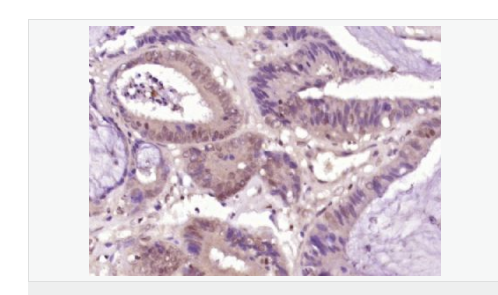

| 產(chǎn)品應(yīng)用 | ELISA=1:5000-10000 IHC-P=1:100-500 IHC-F=1:100-500 IF=1:50-200 (石蠟切片需做抗原修復(fù)) not yet tested in other applications. optimal dilutions/concentrations should be determined by the end user. |

| 免 疫 原 | KLH conjugated synthetic peptide derived from human CDX2/3:151-260/313 |

| 產(chǎn)品介紹 | This gene is a member of the caudal-related homeobox transcription factor gene family. The encoded protein is a major regulator of intestine-specific genes involved in cell growth an differentiation. This protein also plays a role in early embryonic development of the intestinal tract. Aberrant expression of this gene is associated with intestinal inflammation and tumorigenesis. [provided by RefSeq, Jan 2012]. Function: Involved in the transcriptional regulation of multiple genes expressed in the intestinal epithelium. Important in broad range of functions from early differentiation to maintenance of the intestinal epithelial lining of both the small and large intestine. Subcellular Location: Nucleus. Post-translational modifications: Phosphorylation of Ser-60 mediates the transactivation capacity. Similarity: Belongs to the Caudal homeobox family. Contains 1 homeobox DNA-binding domain. SWISS: Q99626 Gene ID: 1045 Database links: Entrez Gene: 1045 Human Entrez Gene: 12591 Mouse Omim: 600297 Human SwissProt: Q99626 Human SwissProt: P43241 Mouse Unigene: 174249 Human Unigene: 20358 Mouse Important Note: This product as supplied is intended for research use only, not for use in human, therapeutic or diagnostic applications. |